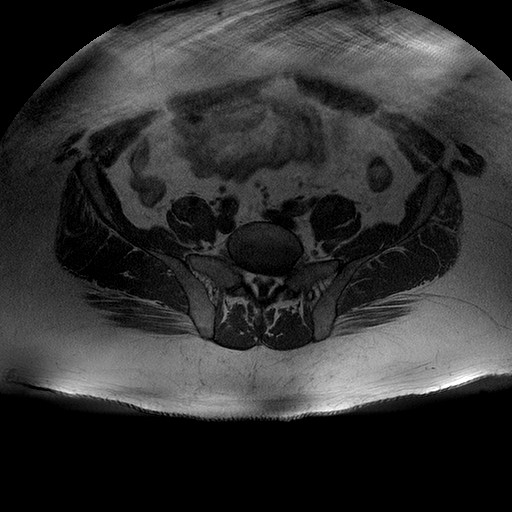

Esami: RMN BACINO

T1W_TSE

Evidenti e simmetriche alterazioni osteofitosiche in regione coxo femorale con riduzione delle rime articolari. Degenerazione completa del cercine glenoideo. Non attuali segni di versamento articolare. Non segni di edema osseo che escludono attuale algodistrofia od osteonecrosi. Lieve e simmetrica riduzione del trofismo della muscolatura glutea.